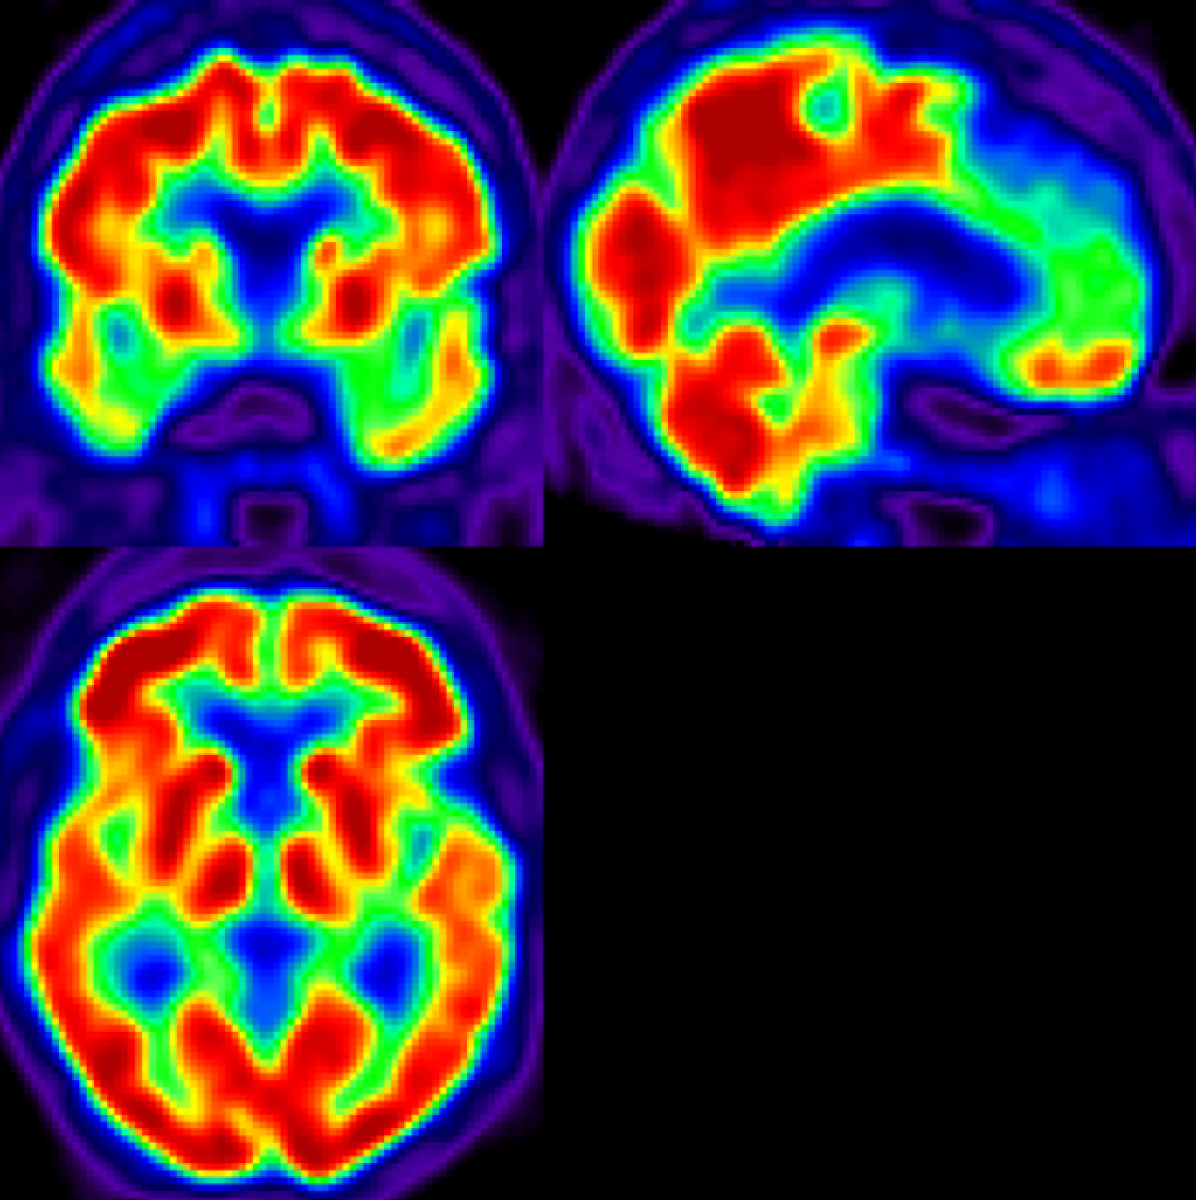

4.2.1 Entire Group

Figure 5 displays obtained results for a comparison between entire CN and AD groups. Upper row displays results using SPM, while lower row shows results obtained using our proposed FDA approach. Results are shown for decreasing α𝛼\alpha levels in both setups. This figure shows that, for any of the selected α𝛼\alpha levels, PET hypo-activity is found in temporal regions and hippocampus. This suggests that these regions are suffering a process of neural loss attributable to AD pathology, findings which go in line with scientific literature on AD pathology [68]. Bear in mind that other regions which could be relevant for AD diagnosis - such as the parahippocampal gyrus and amygdala - are absent in the observed slice.

Results using FDA and SPM show a strong resemblance in terms of regional distribution and point towards hypo-activation patterns in the same regions (i.e. temporal and hippocampal areas), although displaying different extensions. Besides, it is remarkable to observe that our FDA methodology appears to be more resilient to alterations in α𝛼\alpha levels than its counterpart, displaying results which are similar in distribution and extension across the three selected α𝛼\alpha levels. In contrast, SPM appears as a methodology whose results heavily depend on the selected α𝛼\alpha level.

Results using SPM

Refer to caption

(a) α=0.1𝛼0.1\alpha=0.1

(b) α=0.05𝛼0.05\alpha=0.05

(c) α=0.01𝛼0.01\alpha=0.01

Results using FDA

(d) α=0.1𝛼0.1\alpha=0.1

(e) α=0.05𝛼0.05\alpha=0.05

(f) α=0.01𝛼0.01\alpha=0.01

Figure 5: Comparison between classical SPM (uncorrected p-value) and FDA approaches for entire groups: AD (n=51) vs CN (n=75) at different α𝛼\alpha levels. Blue indicates hypo-activation in AD compared to CN while orange indicates hyper-activation.